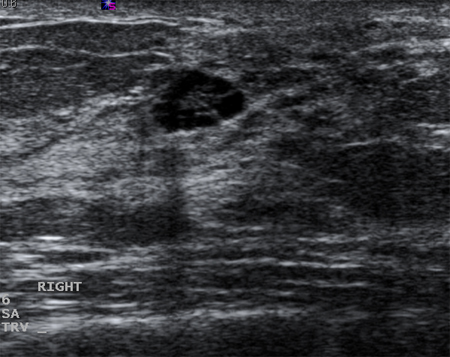

Cysts that recur or do not completely resolve with aspiration should be biopsied to rule out malignancy. Similarly, biopsy should be considered in complex cysts or those with solid elements. Sonographic characteristics may classify a solid mass as either 'probably benign' or 'suspicious'. Masses that are smooth, oval, lobulated, with clearly defined margins, and that are wider than they are tall, are often benign (e.g., fibroadenoma). If a mass is irregular, heterogeneous, has poorly defined or spiculated margins, and is taller than it is wide, it is considered 'suspicious' for malignancy, and biopsy should be undertaken.[Figure caption and citation for the preceding image starts]: Ultrasonographic image of a complex cystCourtesy of Dr Lane Roland, University of Louisville; used with permission [Citation ends].

[Figure caption and citation for the preceding image starts]: Ultrasonographic image of an invasive carcinomaCourtesy of Dr Lane Roland, University of Louisville; used with permission [Citation ends].